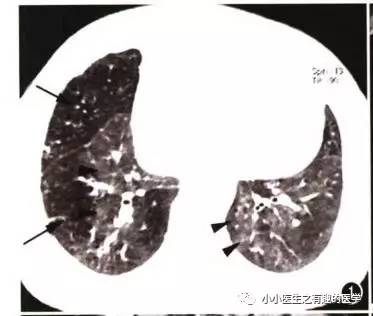

先来说说马赛克。

马赛克征象:由于气道疾病或肺血管性疾病,引起相邻的肺区血液灌注上的差别而出现的不均匀肺密度区,称马赛克灌注。

以图说话,下面都是马赛克,注意了。

马赛克是什么意思,就是马赛克存在的意义?如图

假如CT平扫发现肺部某些地方血管稀疏,灌注不足,千万不要以为没事,有时候,就是肺栓塞,需要警惕。

马赛克,需要警惕肺栓塞,它是肺栓塞的间接表现。并且,在临床中,间断会遇到这样的情况。